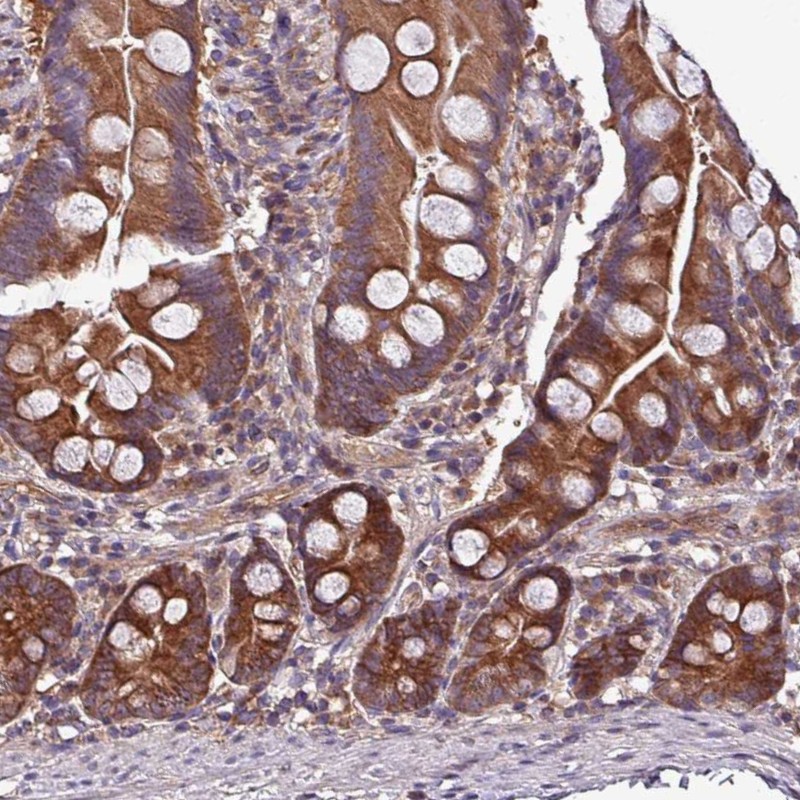

Immunohistochemical staining of human small intestine shows strong cytoplasmic positivity in glandular cells.